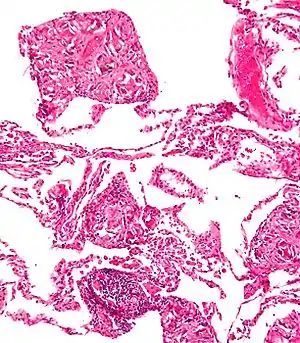

| Pulmonary talcosis. H&E stain. | |